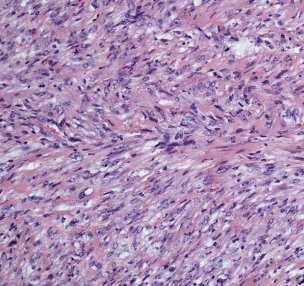

what are the 3 histologic features assessed when grading STS with histopath?

1. differentiation score (0-3)

2. mitotic activity (0-3)

3. tumor necrosis (0-2)

how are the histologic features used to assign a grade to STS?

add the scores of each histo feature up to get grade:

-grade 1= 3 or less

-grade 2= 4-5

-grade 3= 6 or more